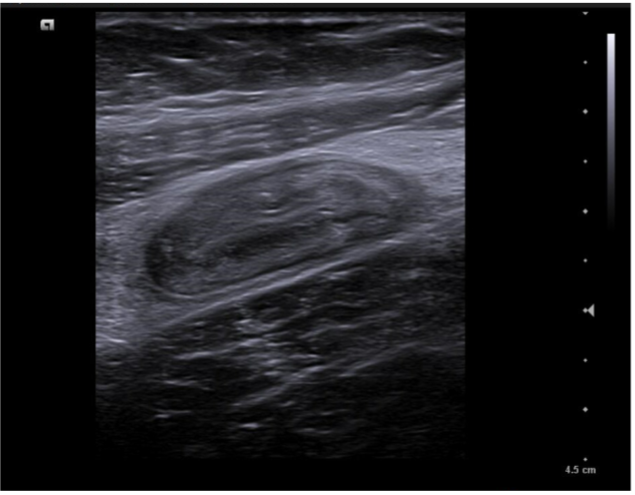

Caso 1. Asa intestinal en FID con poca movilidad (vista con sonda lineal) posible apendicitis.

Caso 2. Asa intestinal fija con edema de pared por posible apendicitis o ileitis. Corte transversal con signo del donut.